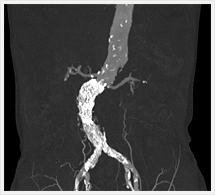

CTでは輪切り像の他にも立体的な画像(3D画像)を作成することもできます。そのためにはより細かくキレイな画像を撮影しなければなりません。当院では64列CTを導入しており、キレイな画像をより細かく撮影することができます。その画像を元に3D画像を作成することによって、より正確な手術のシミュレーションが可能になります。実際に手術をしたときの様子が、手術をする前に画像として見らます。外科系の手術には欠かせない技術となっておりますが、内科系でも血管内手術にも多く利用されております。

当診療放射線技術科では毎日各診療科に対して、その手術に最適な3D画像を提供しております。

以下にその3D画像を一部分紹介します。

腹部・腹部血管